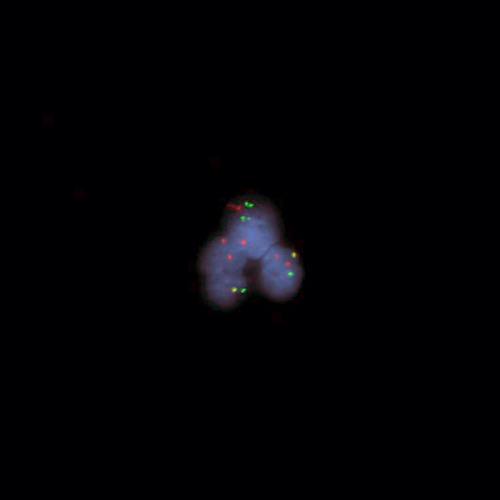

Hybridization of DEK/NUP214 Fusion Probe to a positive cell line showing a fusion due to t(6;9).

The chromosomal translocation t(6;9) (p22;q34) is associated with a specific subtype of acute myeloid leukemia (AML) and constitutes 0.5% to 4% of all AML cases. The translocation results in a fusion between the DEK oncogene (6p22) and the nucleoporin 214 kDa (NUP214 at 9q34; previously known as CAN). The exact mechanism by which the fusion protein DEK-NUP214 contributes to leukemia development has not been identified. Patients with t(6;9) AML have a very poor prognosis. The DEK / NUP214 t(6;9) specific FISH probe has been optimized to detect the reciprocal translocation t(6;9) in a dual-color, dual-fusion assay on metaphase/interphase spreads, blood smears and bone marrow cells.